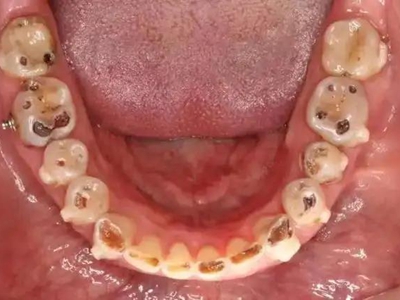

酸蚀症后排牙齿大量缺损图

酸蚀症患者的后排牙齿可发生大量缺损,一侧牙齿遗留圆盘状牙根,形似被切割,另一侧牙齿有大量凹陷坑洞,部分牙齿颜色发黑或呈黄褐色,其发生与长期接触酸性物质有关。

酸蚀症牙齿缺损颜色加深图

酸蚀症患者的牙齿牙冠面会出现多处缺损,下列牙齿均有不同大小的坑洞,表面坑洼不平,缺损处颜色加深,呈黄色至黑褐色,需进行牙齿修复治疗。